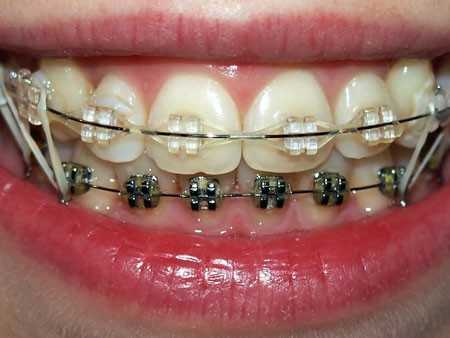

- Брекет-системы. Они способны корректировать прикус при полностью сформировавшемся положении резцов и моляров. Для лечения применяются вестибулярные и лингвальные конструкции;

![]()

Начиная с 12-16 лет, основным методом лечения глубокого прикуса становятся несъемные ортодонтические аппараты – брекеты. У взрослых ортодонтическое лечение глубокого прикуса может сочетаться с хирургическим (компактостеотомией).

Начиная с 11-12-летнего возраста, для коррекции неправильного прикуса у детей могут применяться ортодонтические пластинки - съемные аппараты. С помощью съемных пластинок можно повернуть и переместить зубы, сузить или расширить зубную дугу. Примерно с этого же возраста для исправления неправильного прикуса у детей применяется несъемная аппаратура – брекет-системы, представляющие собой маленькие замочки, с помощью которых каждый зуб соединяется со специальной дугой, корректирующей положение зубов. По окончании основного периода, для закрепления правильного положения зубов, возникает необходимость в ношении ретейнера или ретенционной каппы. Весь период исправления неправильного прикуса у детей с помощью брекет-системы в среднем занимает около 2-х лет.

Установка брекетов

Во время основного этапа коррекции неправильного прикуса производят установку брекетов, для их фиксации используются клеевые композиты. Однако, в зависимости от типа брекетов используются разные методики установки. Каждый вестибулярный брекет наклеивают на переднюю поверхность зубов, которые нуждаются в коррекции, далее на них крепят опорные кольца, а в замочки продевают силовую дугу. Дуга изготавливается из материалов, обладающих эластичностью и упругостью, за счет чего она стремиться занять ту форму, которую ей придали первоначально.

Дефект прикуса лечат при помощи ортодонтических конструкций. Это пластинки и несколько разновидностей систем брекетов. Брекет-системы позволяют довольно эффективно исправлять глубокий прикус.

У детей 12 лет и взрослых прикус изменяют с помощью ортодонтических аппаратов. Аппараты могут быть установлены на передней поверхности зубного ряда (вестибулярные), так и на задней (лингвальные). Указанные устройства относятся к несъемным приспособлениям.

Выбор брекет-систем довольно широк: лингвальные, керамические, саморегулирующиеся, металлические и другие. Какие выбрать, дело каждого.